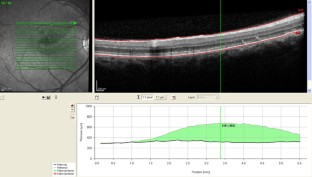

Abb. 1